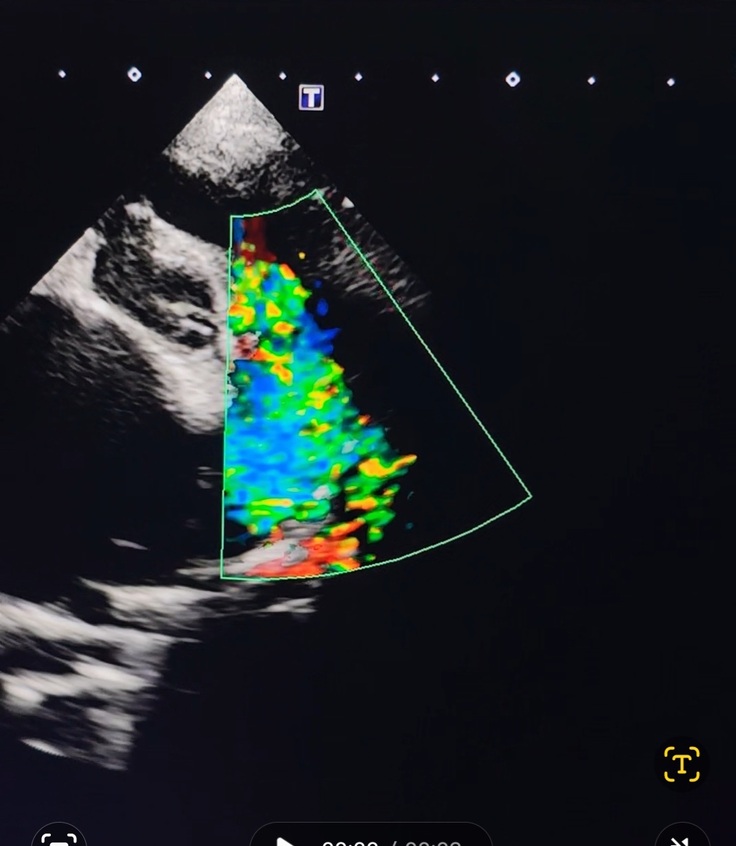

レントゲン、エコー、血液検査全て検査してやっと病名がハッキリしました。

この時既に肺にお水が少し貯まっていました。

病名は『動脈管開存症』生まれて数日で閉じるはずの血管がそのまま残っていて心臓が肥大しているのですが、ここまで大きくなった心臓は本当に数件程度だそうで、肋骨も圧迫し、気管支も背骨に押し付けられる程に大きくなっているのと肺に少し貯まっているお水を出す為に利尿剤と心臓のお薬を頂いて帰って来ました。

心臓が大きくなりすぎて僧帽弁がきっちり閉じられないので逆流のため左心房、左心室拡大。

↑の写真は本来動画で撮ってるのですがその動画はインスタに載せます。

Instagram @wakaba.asahiで下の方にリンク貼っています。

エコーでは縛る血管が太いらしくかなり縛る時に血管が切れる可能性が高いのも事実です。